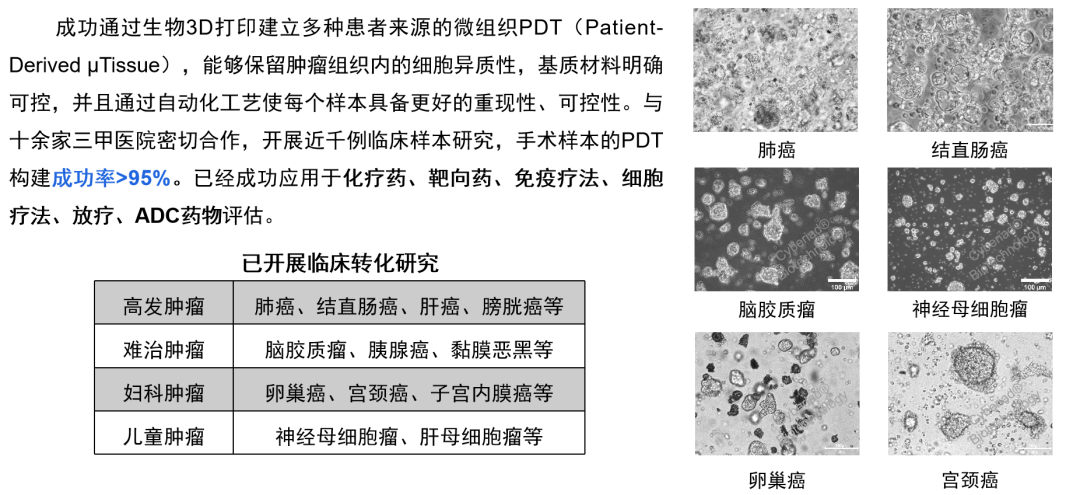

在肿瘤领域,赛箔生物与临床合作者共同研发基于生物3D打印技术与生物材料的肿瘤微组织(PDT),包括高发肿瘤、难治肿瘤、妇科肿瘤和儿童肿瘤四大类,涵盖肺癌、肠癌、脑胶质瘤、胰腺癌、卵巢癌、子宫内膜癌、宫颈癌、神经母细胞瘤、肝母细胞瘤等实体瘤。通过逾千例样本研究,充分证实了PDT与患者组织具有高度一致的分子特征和药物敏感性,为肿瘤药物筛选提供了丰富多样且精准的实验模型。